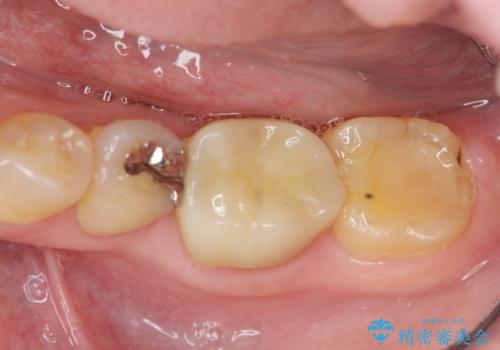

- 銀歯の部分で噛むと痛い、痛みが増している、と治療を希望され来院されました。

根管治療を行ったのち、噛んだときに生じていた痛みも改善し、またしっかりと噛んで食事ができるようになりました。